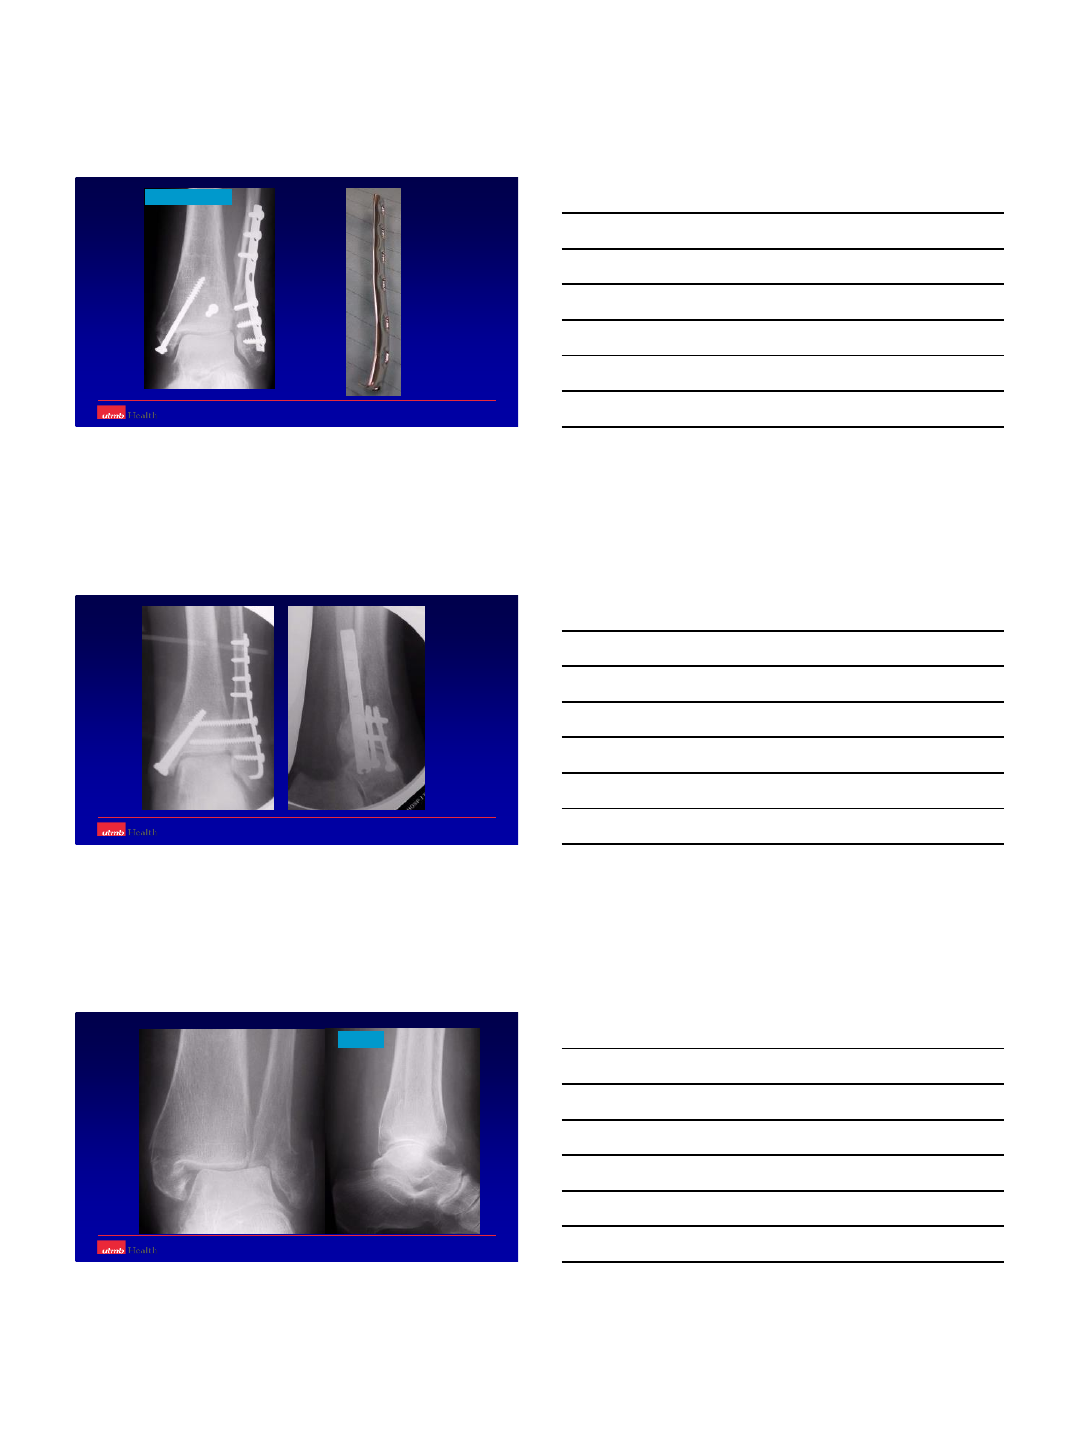

Prone position

8

Prone position ‘strange’ for MM

13

Oblique fracture plane

Sloppy lateral with platform for leg

PM + LM MM